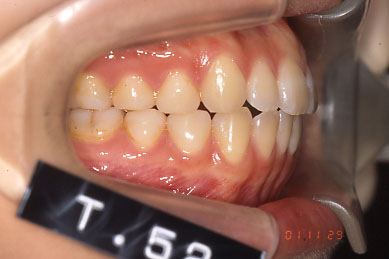

After右側貌

Before

Afterリボン歯科・矯正歯科グループは、インビザライン矯正の高精度、スピーディ、快適な治療の為にiTero(口腔内スキャナ)をグループで18台導入しております。